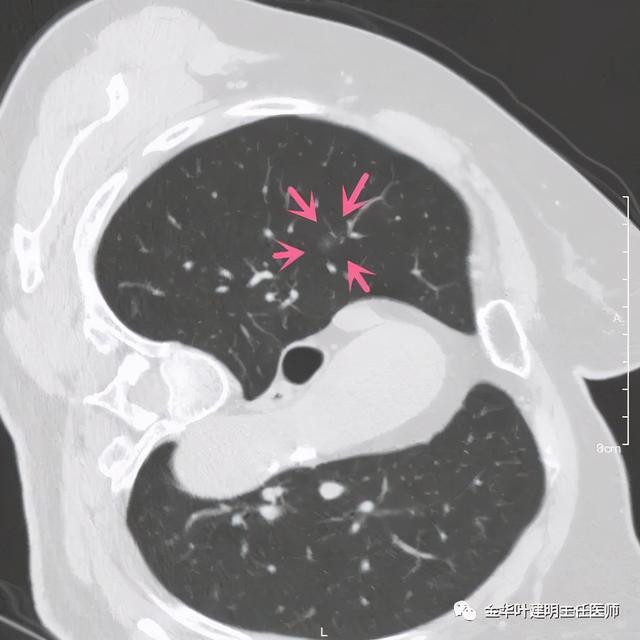

患者为女性 , 今年76岁 , 平时体质甚好 , 家务及地里劳动都胜任 , 头发仍乌黑(我自己倒有一半白发了) 。 肺功能与血气分析正常 。 CT检查图像如下:

可见右肺上叶混合磨玻璃结节 , 有明显分叶征 , 瘤肺边界虽然欠清楚 , 但轮廓比较清晰 。 看着也许会考虑炎性 , 但总觉得其比较僵硬 , 看去不舒服 。 这种病灶一是如果持续存在就极可能是肺癌 , 二是靶扫描显示更清晰的细节 , 如果瘤肺边界还是清楚的 , 也基本是肺癌 。 我们回顾发现其于2019年3月在我们医院做过CT平扫 , 当时报告如下:

靶扫描更清楚显示瘤肺边界较清、分叶及密度不均杂乱 , 并有少许胸膜牵拉凹陷 , 当然考虑是肺癌 , 而且应该是浸润性腺癌了 。 其长径达2.5厘米!靶扫描还发现了平扫没被注意到的另一个病灶: